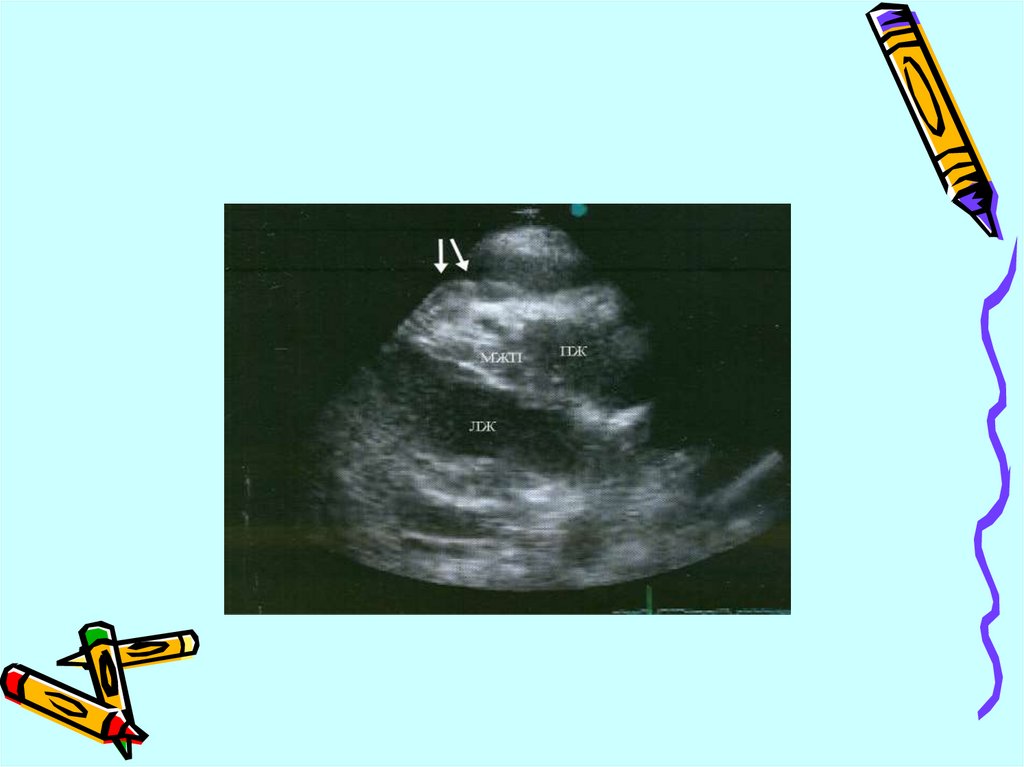

ЭКГ изменения

Нарушение локальной